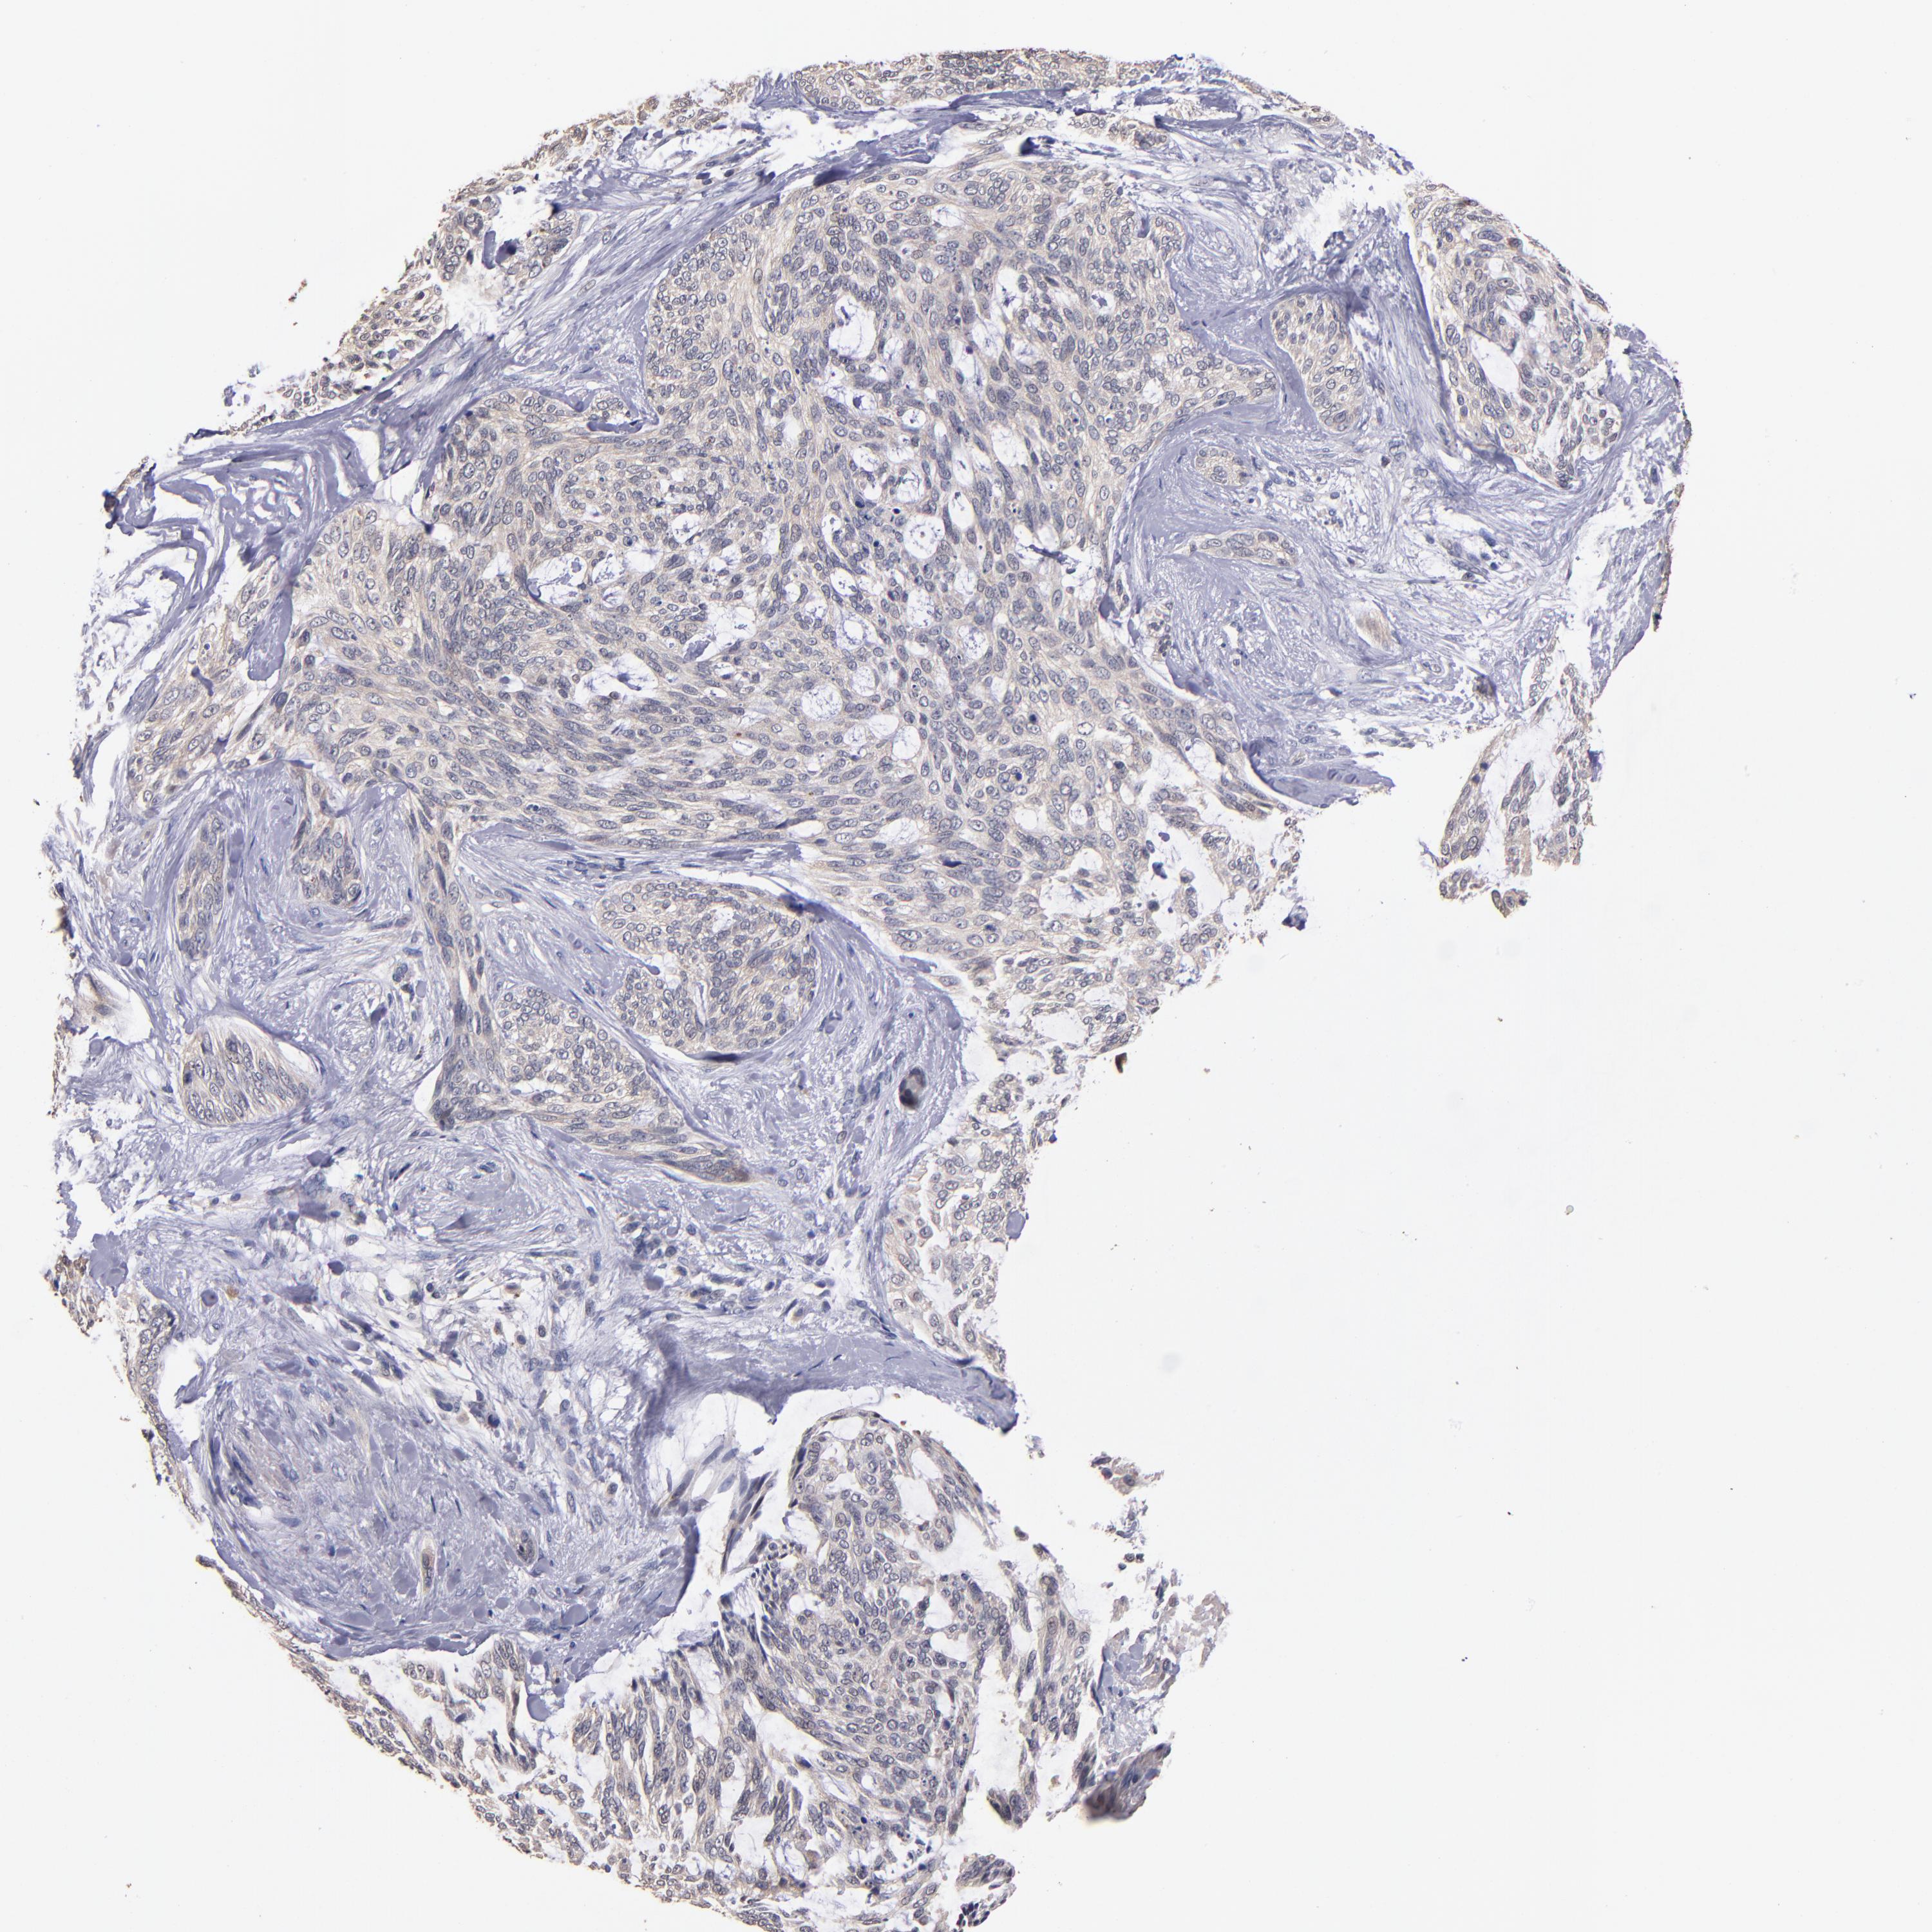

SKIN CANCER - Protein expressioni

A mouse-over function shows sample information and annotation data. Click on an image to view it in a full screen mode. Samples can be filtered based on level of antibody staining by selecting one or several of the following categories: high, medium, low and not detected. The assay and annotation is described here.

Each image is clickable and will lead to virtual microscopy that enables deeper exploration of all samples and also displays staining intensity scores, fraction scores and subcellular localization as well as patient and tissue information for each sample.

Antibody CAB046029

Squamous cell carcinoma, NOS